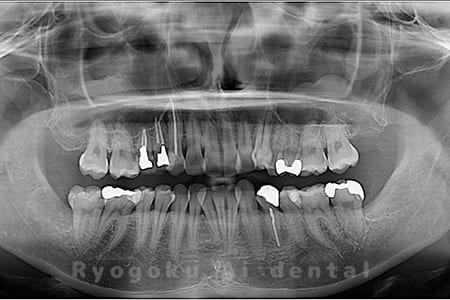

Case03

- 原因

- 上顎、下顎の親知らず

- 治療内容

- 上下4本の親知らずを抜歯したケースです。

<リスク・副作用>

手術後は痛み、腫れ、痺れなどの副作用が生じる場合があります。